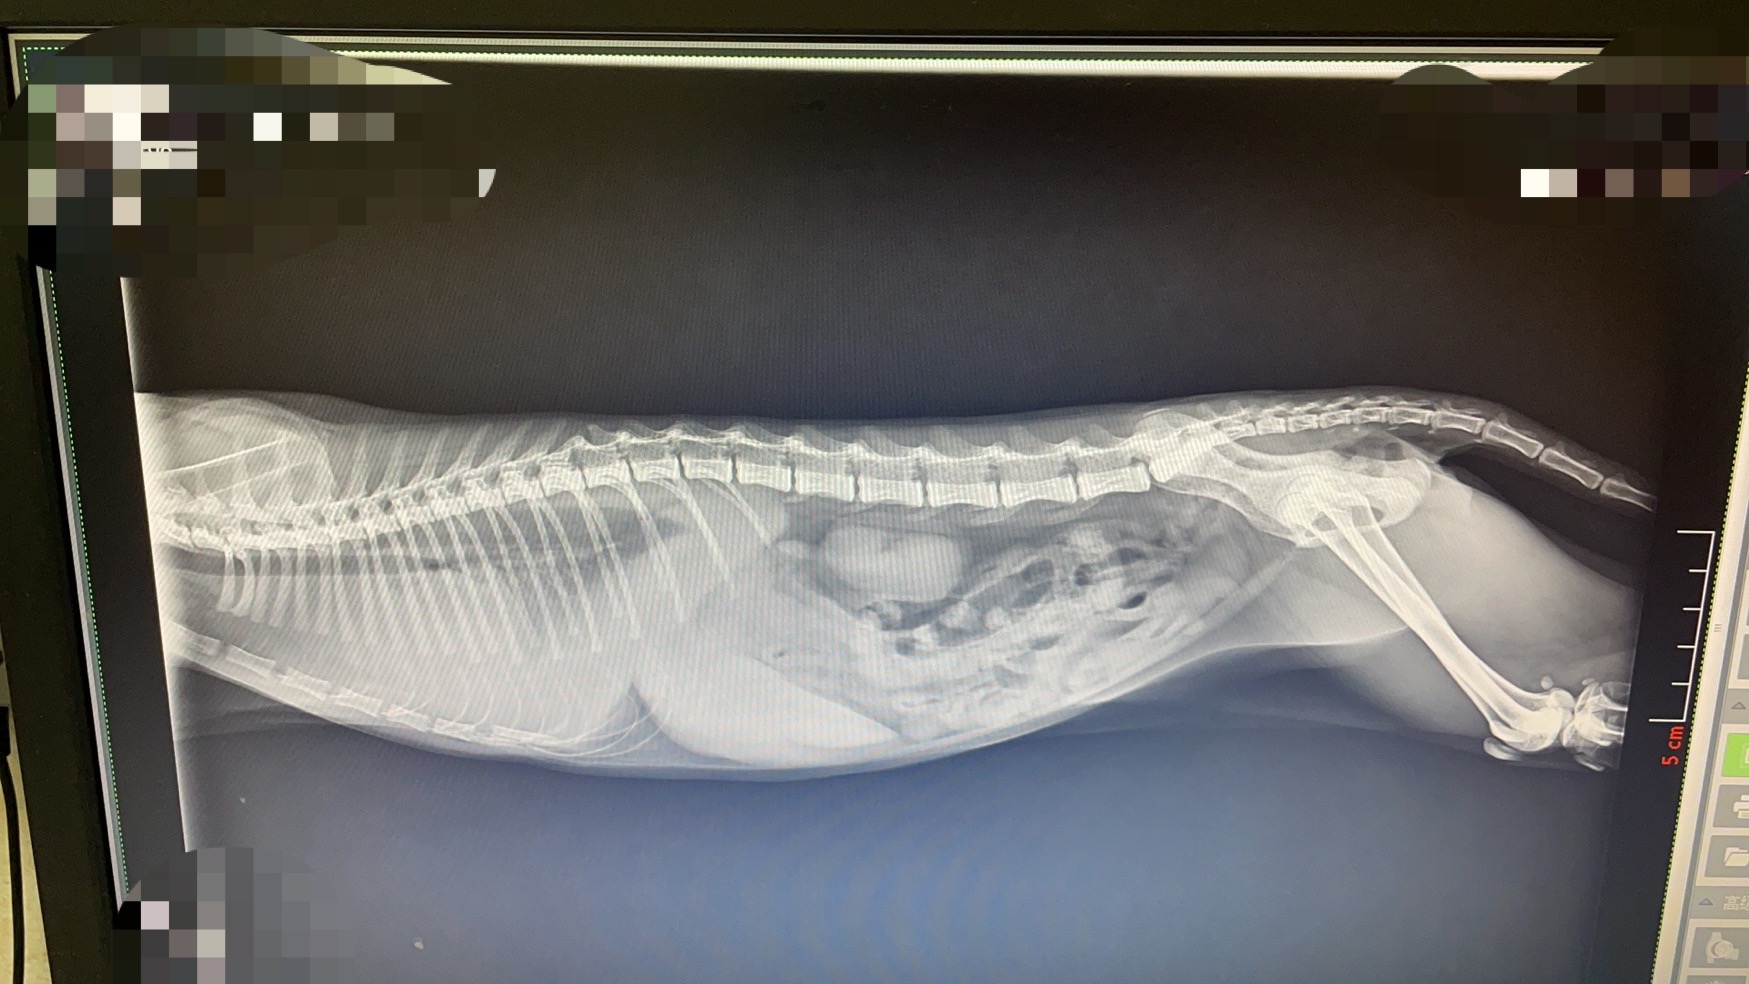

很快收到了医生发过来的图片,情况已经十分危急,她的肺部有大量的胸腔积液,挤压得她的肺都有点变小了,呼吸困难,需要马上做穿刺胸腔做积液检查,医生友情提示了一下要不少费用。当时我能做的只有和医生说,麻烦先救她,至于账单后面想办法了。不过还是请求医生费用如果能优惠的话,请尽量优惠。医生也表示了他的理解。

不过随着胸腔积液被抽出,肺部压力减少,七仔的情况开始稳定下来,医生也说还好今天送来了,在拖就一点估计就不行了。随之而来还有医生发过来的账单~七天的吸氧检查➕刚刚的穿刺和接下来可能需要的穿刺➕5张拍片➕住院期间的营养品、开胃针和消炎药➕七天的猫传腹的特效药441等,打完七折后,加起来大概3000大洋。这咬咬牙也还好,只不过后续需要的441真的,让人头疼。现在想起来,还好七仔还是一直瘦弱的小猫,一次需要的剂量不算太大。